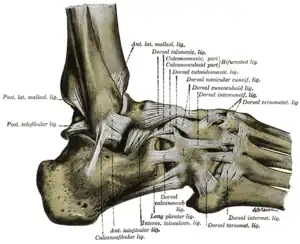

- There is any pain in the malleolar zone; and,

- Bone tenderness along the distal 6 cm of the posterior edge of the tibia or tip of the medial malleolus, OR

- Bone tenderness along the distal 6 cm of the posterior edge of the fibula or tip of the lateral malleolus, OR

- Bone tenderness at the base of the fifth metatarsal (for foot injuries), OR

- Bone tenderness at the navicular bone (for foot injuries), OR